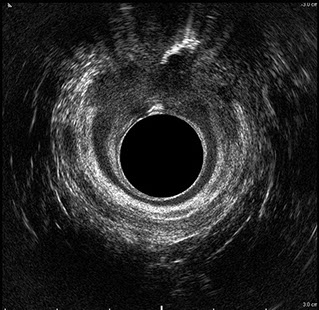

L’ecografia transanale è un esame diagnostico per immagini che consiste nell’introduzione di un trasduttore ad ultrasuoni. Le immagini qualitativamente migliori del canale anale sono ottenute usando un trasduttore rotante, montato in un manipolo rigido, che fornisce un’immagine a 360°. Con le apparecchiature più moderne è anche possibile ottenere immagini tridimensionali.

L’ecografia transanale permette di distinguere la sottomucosa che riveste il canale anale, lo sfintere anale interno, e lo sfintere anale esterno.

Le principali indicazioni all’esecuzione di tale esame sono lo studio dell’integrità delle strutture muscolari nei casi di incontinenza fecale, lo studio topografico dei processi settici perianali (ascessi e fistole) e lo studio dei processi proliferativi epiteliali (carcinoma anale).